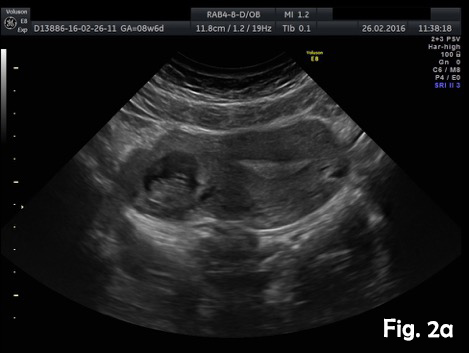

A 39-year-old woman presented for a routine dating scan at 8 weeks 6 days amenorrhea. At examination she also was asymptomatic. Ultrasound examination revealed an empty uterine cavity with a regular endometrium and a gestational sac with a viable embryo located in the interstitial portion of the right fallopian tubes, separate and greater than 1 cm from the lateral edge of the uterine cavity (Fig.2a). The sac was surrounded by a thin myometrial mantle (Fig.2b). Color Doppler sonography revealed peritrophoblastic blood flow around the gestational sac and heart movements (Video 1). No fluid was seen in the pouch of Douglas. Bulging of the outer contour of the uterus in the cornual region was shown on 3D ultrasound (Fig.2c). Laparotomy with excision of the interstitial portion of fallopian tube and right cornual part of the uterus was performed. The postoperative period was uncomplicated.

Figure 2a. Abdominal ultrasound (transverse view). Empty uterine cavity with a regular endometrium and a gestational sac located in the right interstitial area of the uterus.